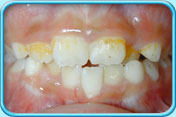

牙齒壞死

因碰撞或蛀牙導致牙齒壞死,壞死的牙髓所釋出的物質滲入象牙質,牙齒就會逐漸呈灰黑色。

治療方法

這類因牙髓壞死而引致的牙齒變色,必須以根管治療(牙髓治療) 處理。